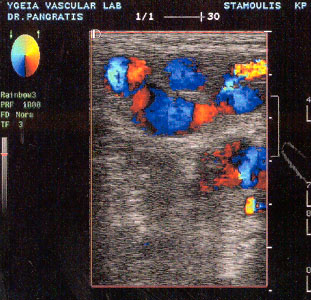

Καθώς ο εξεταστής προχωρεί περιφερικότερα, η σαφηνής αποχωρίζεται και γίνεται

πιο επιφανειακή, ενώ ακολουθούμε όλη την πορεία της επιπολής μηριαίας φλέβας

(εικόνα 3).